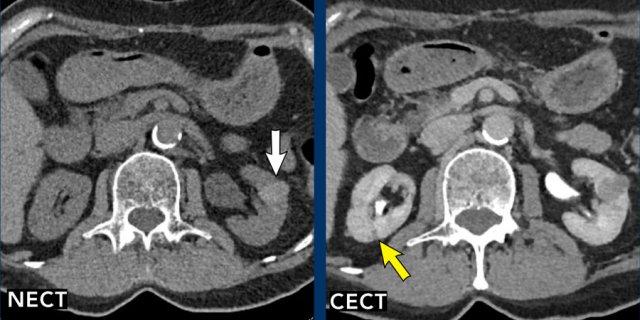

Hình ảnh

Tổn thương 1 (mũi tên vàng)

Quan sát thấy một tổn thương đồng nhất, giảm tỷ trọng ở mặt sau thận phải. Tổn thương này quá nhỏ để phân loại và được xếp vào nhóm Bosniak II.

Tổn thương 2 (mũi tên trắng)

Trên CT không tiêm thuốc cản quang (NECT), có một tổn thương tăng tỷ trọng ở thận trái với HU > 70, thông thường tương ứng với tổn thương Bosniak II (mũi tên trắng). CT có tiêm thuốc cản quang (CECT) trong pha tĩnh mạch cửa không cho thấy sự ngấm thuốc đáng kể nhưng có hình ảnh không đồng nhất.

Trường hợp này cần chụp thêm MRI để đánh giá bổ sung (xem hình ảnh tiếp theo).

MRI của cùng bệnh nhân.

Tổn thương giảm tín hiệu trên chuỗi xung T2W và tăng tín hiệu trên chuỗi xung T1W.

Không có ngấm thuốc tương phản từ trên chuỗi xung trừ (subtraction).

Trên MRI, tổn thương được xác nhận là Bosniak II.